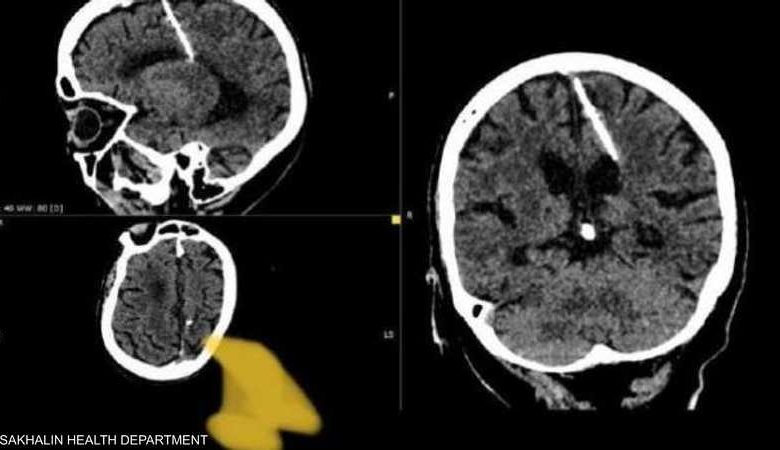

عثر أطباء خلال فحص بالتصوير المقطعي على إبرة بطول ثلاثة سنتيمترات موجودة منذ ثمانين عاماً داخل دماغ امرأة مسنّة في أقصى الشرق الروسي.

وقالت إدارة الصحة المحلية “لقد اخترقت الإبرة الفص الجداري الأيسر، لكن لم يكن لها التأثير المقصود، إذ نجت الفتاة”.